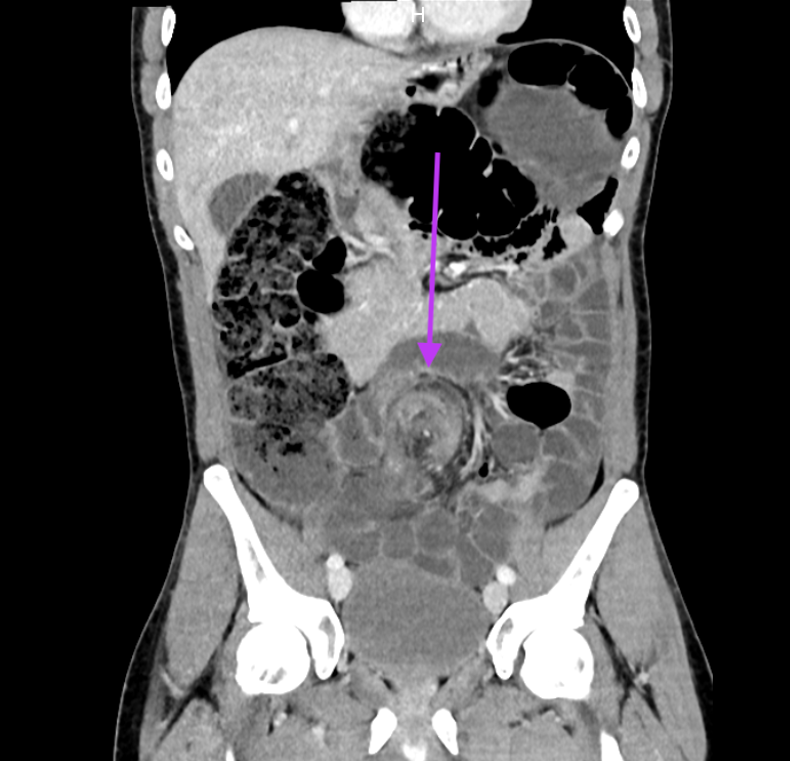

Ce scanner met en évidence un signe de Whirlpool (ou Whirl) qui représente la torsion du mésentère du sigmoïde et des vaisseaux mésentériques, diagnostic dans ce cas de volvulus du sigmoïde. On constate une dilatation en amont de l'ensemble du cadre colique et de quelques anses iléales avec stase colique importante, sans signes de souffrance intestinale.

Les occlusions basses représentent 25-35 % de l’ensemble des occlusions digestives, les causes principales étant le cancer colique, la sigmoïdite diverticulaire et le volvulus colique. Le volvulus du sigmoïde, 6% des occlusions intestinales, correspond à la torsion du sigmoïde autour de son méso avec un degré de rotation de 180 à 360° et touche essentiellement les sujets âgés, peu mobiles, constipés chroniques. Il existe des prédispositions anatomiques chez certains sujets (dolichocôlon : boucle sigmoïdienne longue, mobile, congénitale) et une prédisposition masculine.